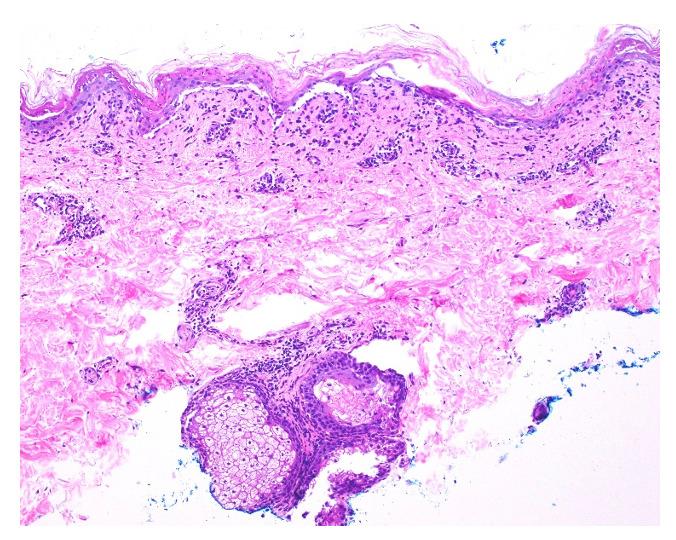

A 36-year-old man with a history of arthritis, initially diagnosed as seronegative rheumatoid arthritis, developed new-onset SLE complicated by HLH and TEN. The patient presented with fevers, abdominal pain, vomiting, fatigue, rash, and significant weight loss. Despite multiple hospital visits and antibiotic treatments, his symptoms persisted. On admission, he exhibited extensive erythema, targetoid macules, full-thickness desquamation, and hemorrhagic crusting, covering about 30% of his body surface area. Laboratory findings revealed pancytopenia, positive ANA, anti-chromatin, dsDNA, hypocomplementemia, elevated ferritin, and hypertriglyceridemia. Skin biopsy showed interface dermatitis with full-thickness necrosis, and bone marrow biopsy confirmed hemophagocytic histiocytosis. The patient was diagnosed with SLE, HLH, and TEN and was treated with high-dose prednisone, IVIG, hydroxychloroquine, and mycophenolate mofetil, leading to significant improvement. This case highlights the complexity of diagnosing and managing concurrent SLE, HLH, and TEN. Early recognition and a multidisciplinary approach are crucial for effective treatment and improved outcomes. The patient's positive response to immunosuppressive therapy underscores the importance of addressing the underlying autoimmune condition in such complex presentations.

一名36岁的男性,有关节炎病史,最初被诊断为血清阴性类风湿关节炎,后来发展为新发系统性红斑狼疮(SLE),并伴有噬血细胞性淋巴组织细胞增生症(HLH)和中毒性表皮坏死松解症(TEN)。患者出现发热、腹痛、呕吐、疲劳、皮疹和显著体重减轻。尽管多次住院并接受抗生素治疗,但其症状仍持续存在。入院时,他表现出广泛的红斑、靶形斑疹、全层脱皮和出血性结痂,覆盖约30%的体表面积。实验室检查结果显示全血细胞减少、抗核抗体(ANA)阳性、抗染色质抗体、双链DNA(dsDNA)阳性、补体降低、铁蛋白升高和高甘油三酯血症。皮肤活检显示界面性皮炎伴全层坏死,骨髓活检证实为噬血细胞性组织细胞增生症。该患者被诊断为SLE、HLH和TEN,并接受了大剂量泼尼松、静脉注射免疫球蛋白(IVIG)、羟氯喹和霉酚酸酯治疗,病情有显著改善。本病例突出了诊断和管理并发SLE、HLH和TEN的复杂性。早期识别和多学科方法对于有效治疗和改善预后至关重要。患者对免疫抑制治疗的积极反应强调了在这种复杂情况下解决潜在自身免疫性疾病的重要性。